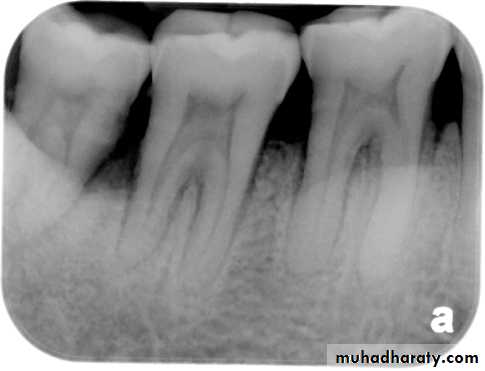

• Clinically:“Pink Tooth” appearance• Radiographic changes:

– Radiolucent enlargement of pulp canal

– Original root canal outline distorted

– Bone changes are seen only when root perforation into periodontal ligament takes place.